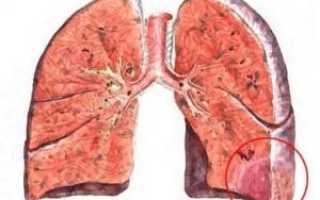

Тромбоэмболия легочных артерий нередко приводит к ишемизации легочной паренхимы. В результате поврежденная ткань легкого переполняется кровью, которая поступает из зон с нормальной васкуляризацией. Развивается геморрагический инфаркт легкого.

На участке воспаления создаются оптимальные условия для развития инфекции, что провоцирует возникновение симптомов инфаркт-пневмонии. Если ветвь легочной артерии перекрывается инфицированным тромбом, отмечается деструкция паренхимы, формируется абсцесс легкого.